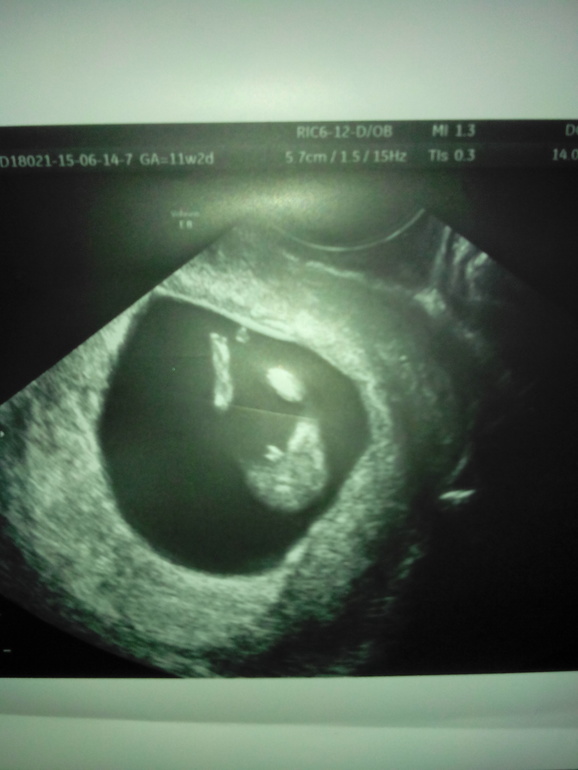

НАм сказали, что скорее мальчик)) на 11.2